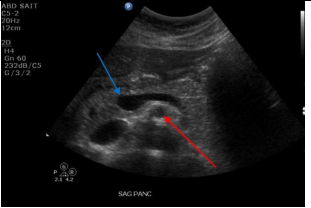

Label the Blue and red arrows

A

Blue: Portal confluence

Red: SMA